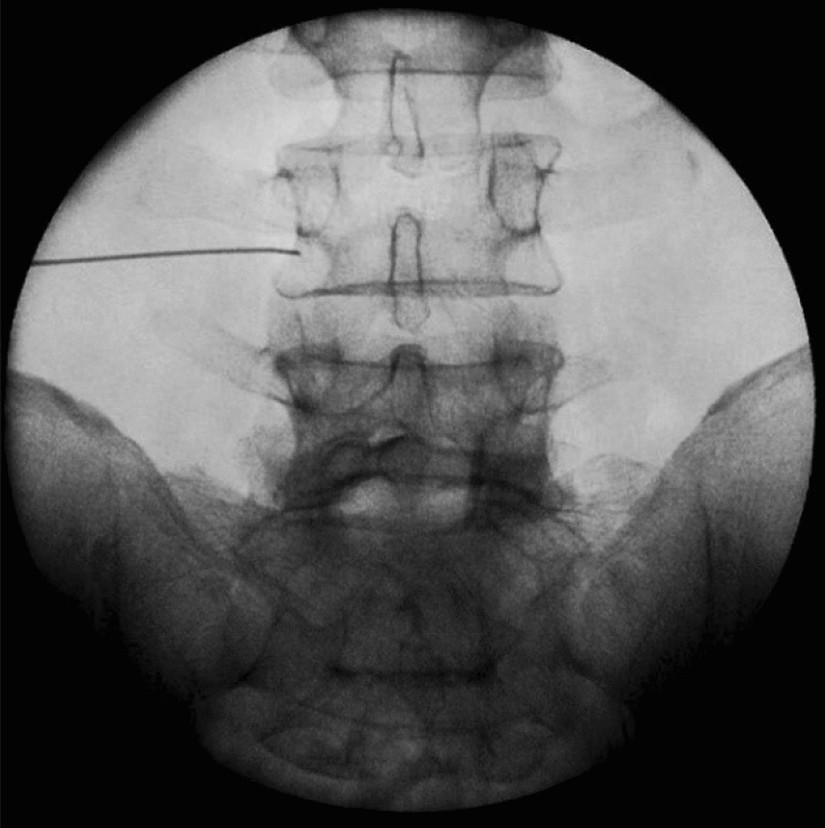

Transforaminal Nerve Root Block

A minimally invasive procedure involving an injection of a local anesthetic and corticosteroid into the spinal nerve's exit point. It treats sciatica, herniated discs, and spinal stenosis, reducing inflammation and improving mobility.